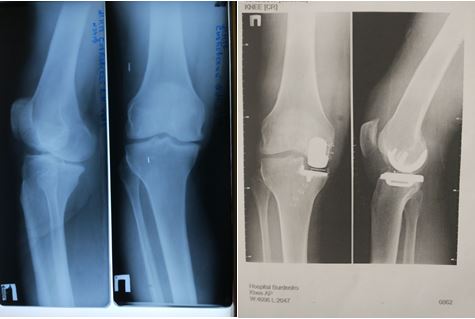

Поскольку госпиталь – это один из головных учреждений Министерства обороны, в нем наблюдаются больные с самой сложной патологией, требующей выполнения операций по замене суставов. Специалисты Центра Травматологии и Ортопедии им. Н.Н. Бурденко имеют значительный опыт лечения пациентов с тяжелыми поражениями суставов, позволяющими поставить больных на ноги даже в самых безнадежных случаях, например, при гонартрозе.

Гонартроз – это тяжелое заболевание коленного сустава, при котором разрушается суставной хрящ, появляются боли и ограничения движений. Консервативное лечение, как правило, малоэффективно и позволяет лишь незначительно уменьшить боль, не влияя на сам патологический процесс.

В некоторых случаях возможен малотравматичный и малоинвазивный вариант лечения – одномыщелковое эндопротезирование коленного сустава. Он подразумевает замену не всего сустава на эндопротез, а его наиболее изношенной части.

Одномыщелковое эндопротезирование показано при изолированных поражениях наружного или внутреннего отделов коленного сустава.

Данная процедура выполняется в Центре Травматологии и Ортопедии ГВКГ им. Н.Н. Бурденко в течение последних 5 лет. В своей работе врачи применяют качественные эндопротезы фирмы Zimmer Biomet. Широкий ассортимент имплантатов дает возможность подобрать эндопротез с учетом возраста пациента, его физической активности, а также характера и тяжести заболевания или травмы. Современное и высококачественное оборудование Zimmer Biomet позволяет получить отличные результаты операций и поставить на ноги даже самых тяжелых больных.